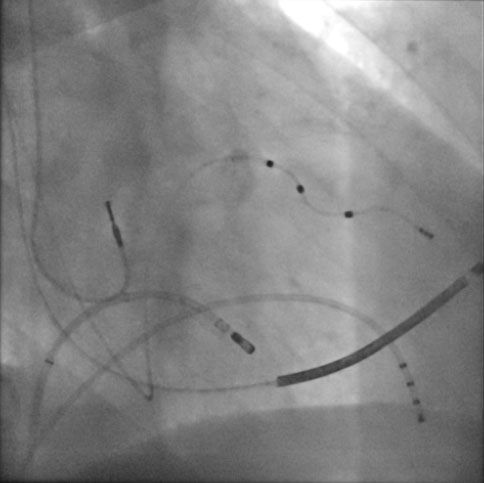

After local anesthesia in the femoral site, the Seldinger technique is followed by cannulation of the right femoral vein. Through this venous access, a scaler catheter is advanced near the atrium ventricular node (compact part). By delivering radiofrequency, electrical communication between the atria and ventricles is interrupted, thus allowing the implanted device to stimulate the heart at the desired frequency.